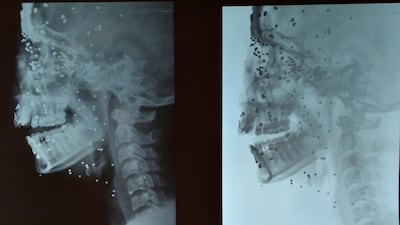

The guns shoot small metal balls, slightly larger than a grain of sand and sometimes covered in rubber. Indian forces use both the plain metal balls and the rubber-coated ones, which are designed to minimise damage. One cartridge can pack as many as 600 pellets, which are sprayed out in every direction at high speeds of over 1,000 feet per second.

But while the Indian army claims that pellet guns – classified as Kinetic Impact Projectiles (KIPS) – are non-lethal weapons, a report this year by Physicians for Human Rights said that KIPs “have the same ability to penetrate the skin as conventional live ammunition and can be just as lethal”.

“When launched or fired from afar, these weapons are inaccurate and strike vulnerable body parts, as well as cause unintended injuries to bystanders,” the report said.

Mr Chadha also pointed out that if pellets guns were fired from close range, or at sensitive parts of the body such as the face, “they tend to do far more damage, as we’re seeing in Kashmir”.

Many pellet victims have suffered tiny, hard-to-treat fractures in their skulls, as well as irreversible damage to their eyes. On Wednesday the Indian government sent three eye specialists to Srinagar to treat eye injuries from pellets.

One of the victims is 14-year-old Insha Malik, whose photograph revealing swollen eyes and a face covered in puncture wounds was circulated widely on social media on Thursday. Insha was looking out of her open kitchen window at clashes in the street on Tuesday when dozens of pellets struck her face. After operating on her, doctors told Kashmiri newspapers that her vision was unlikely to return. Separately, a number of pellets remain lodged inside Insha’s head, too deep to remove and still liable to cause further damage.